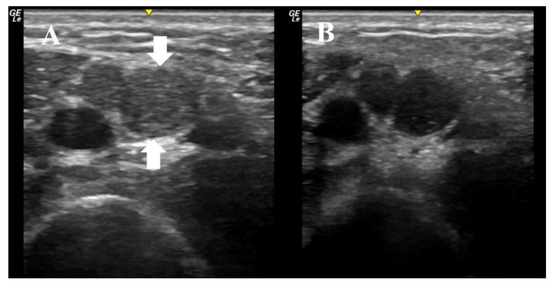

6. Illustrative Case